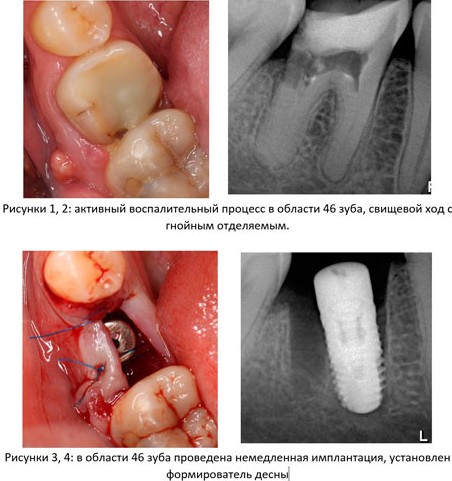

1. Стадия воспалительного процесса. За редким исключением большинство зубов удаляются из-за развитого воспалительного процесса (периодонтита) и невозможности его терапевтического лечения и/или реставрации зуба цивилизованными методами. Ремиссия или хроническое течение заболевания говорит о том, что организм «справляется» с воспалительным очагом – и с этой точки зрения, наличие даже обширного периапикального процесса не является противопоказанием к установке импланта в лунку зуба. И наоборот, обострение периодонтита, болевой синдром, гноетечение и т. п. является противопоказанием к немедленной имплантации.

Это, разумеется, относительно, потому степень риска оценивается в каждом конкретном клиническом случае (рис. 1-4):

Другими словами, до определенных пределов (каких – рассматривается индивидуально) даже острый воспалительный процесс не является абсолютным противопоказанием для операции немедленной имплантации.